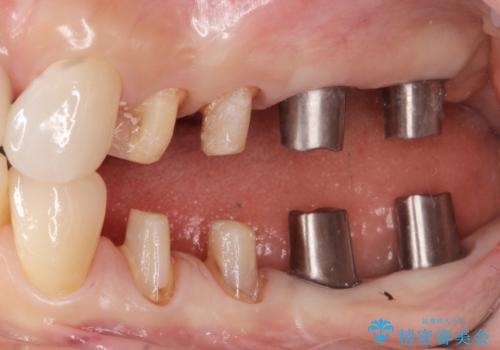

全顎 虫歯 インプラント治療

- 長年悩んでいる歯の見た目や欠損を全て治療したい、と希望され来院されました。

不適合やすり減ったクラウンを全て除去し、虫歯を丁寧に除去したのち精密なセラミック治療を行いました。

また失ってしまった奥歯についてはインプラントを用いて噛み合わせを確立する治療方針としました。